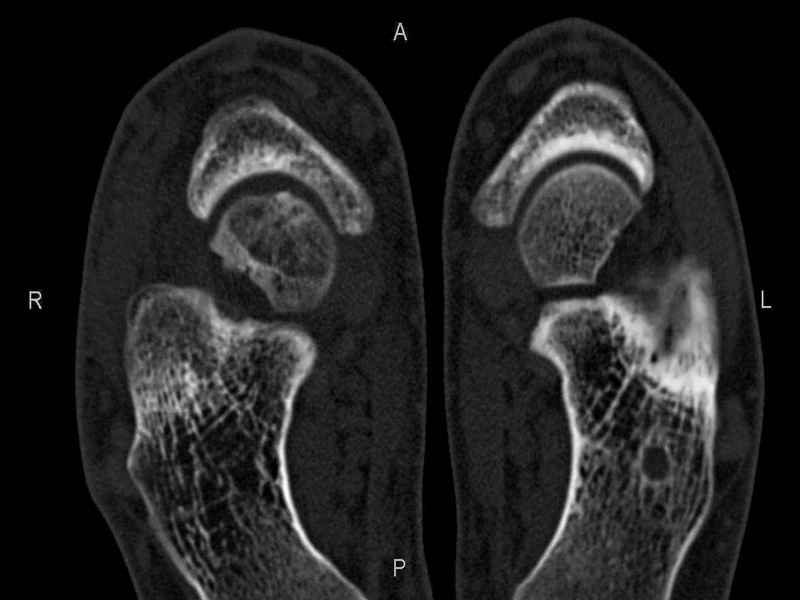

Рассекающий остеходрит + киста шейки тарана

Уважаемые коллеги, обратился за помощью пациент, мужчина, 25 лет. С жалобами на болевой синдром в области голеностопного сустава и среднем отделе стопы.

Травму отрицает. Со слов, болевой синдром в течении 1 года. Последние 1-1.5 мес периодически вынужден пользоваться костылями. После ограничения нагрузки боли уменьшаются. Соматически здоров. До появления болей активно занимался рукопашным боем.

На СКТ картина рассекающего остеохондрита блока таранной кости, киста шейки таранной кости с признаками импрессии суставной поверхности. А также - разрастания переднего края б\берцовой кости сопровождающиеся клиникой импиджмент синдрома.

Предполагаемый план лечения- удаление свободного фрагмента суставного хряща из трансмаллеолярного доступа с рассверливанием поверхности дефекта, кюретаж кисты шейки с заполнением полости биокомпозитом + дебридмент переднего отдела голеностопного сустава.